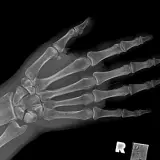

MSK Radiographs

Peds Radiographs